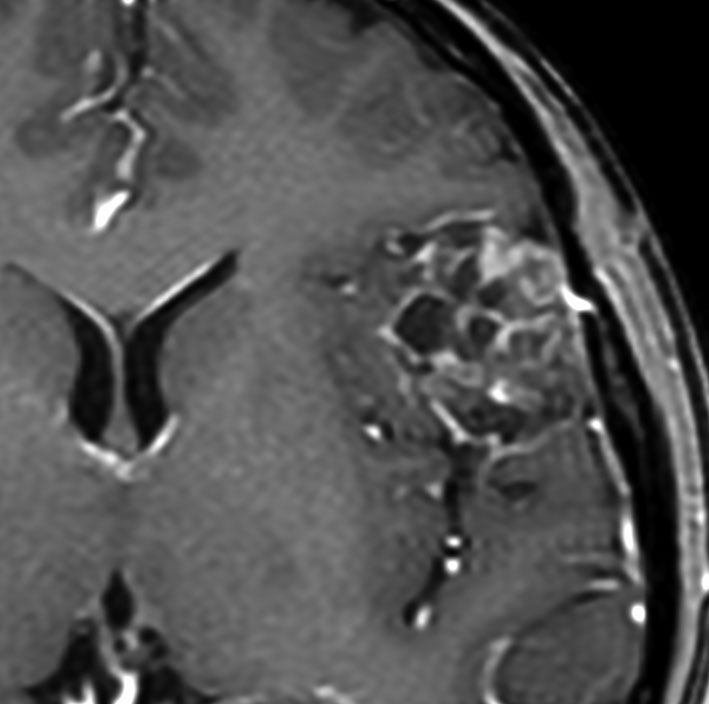

chordoid meningioma WHO grade 2 脊索腫様髄膜腫

この例は鞍結節に発生した髄膜腫で,T2強調画像では高信号が目立ちましたが骨浸潤はなく,一般的なgrade 1 meningiomaとの鑑別はできませんでした。粘液を含む腫瘍で、好酸性の胞体を持つ紡錘形ないし類円形核の細胞がmyxoid / chordoid matrixに浮遊している所見です。腫瘍細胞が固まる部分は典型的な髄膜腫の特徴をよく表す組織構造です。胞体内には空胞変性 vacuolated cells が認められました。MIB-1 5%, EMA (+), Cam5.2 (-)。珍しいタイプで,概して大きな髄膜腫としてテント上に発見され,手術後の再発率は高いのでグレード2とされます。Wangは30例中の5例に再発を見たとしていますから全摘出できればそれほど高い再発割合ではありません。

Castleman’s diseaseをはじめhematological conditions / diseasesとの合併や小児例例が多いとされましたが,実際には特発例,孤発例が多いです。